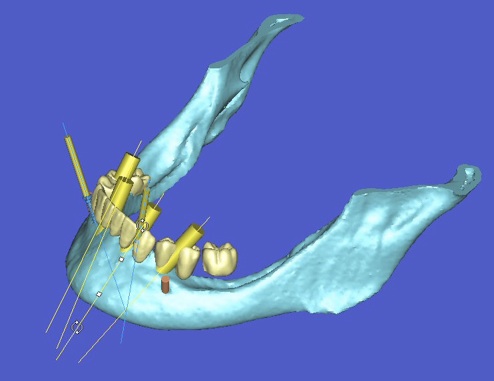

l’informatique au service de l’implantologie

La société Materialise a développé un logiciel SIMPLANT qui permet de simuler la position des futurs implants et de les transférer en bouche à l’aide d’un guide chirurgical.